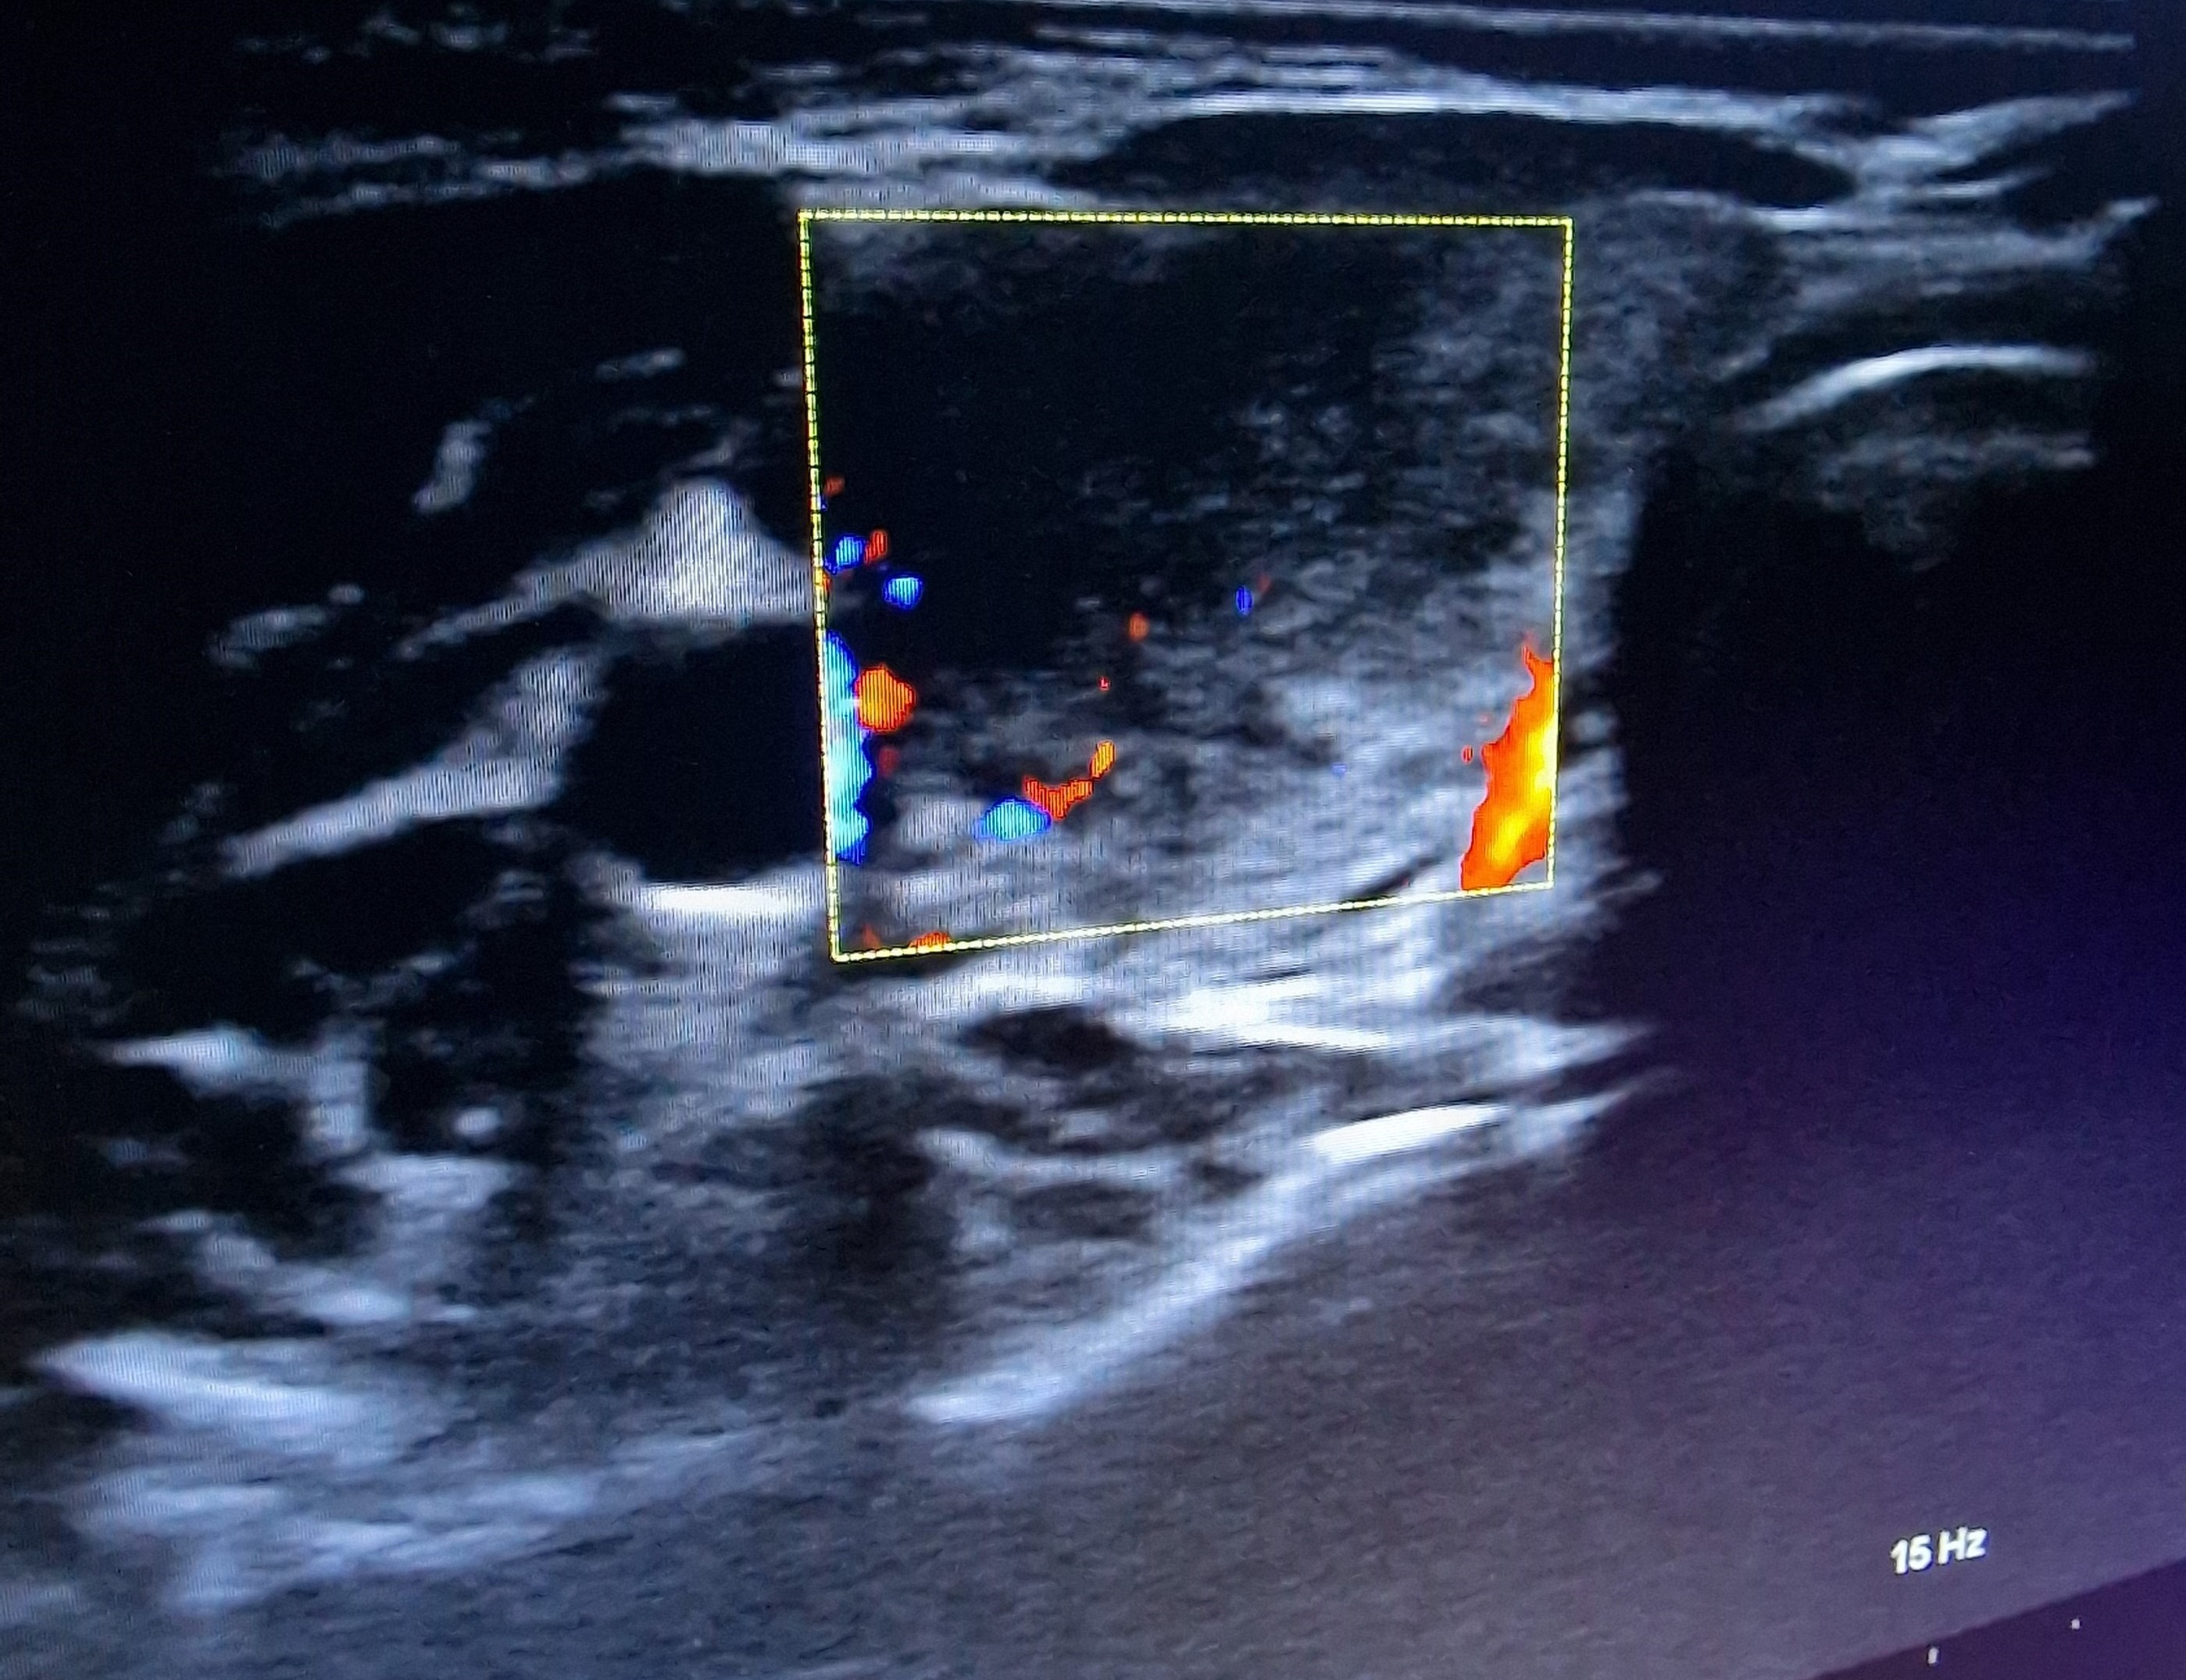

Ecografía cervical: tiroides de ecogenicidad heterogénea con áreas hipoecogénicas y ausencia de vascularización de éstas, Lóbulo Tiroideo Derecho 20 x 14 mm con nódulo < 10 mm no maligno e izquierdo 16 x 12 mm.

El diagnóstico diferencial se realizará con procesos infecciosos de vías respiratorias altas, con tiroidopatías con hipertiroidismo y ecogenicidad disminuida (enfermedad de Graves, patrón hipervascular; tiroiditis supurativa aguda), carcinoma tiroideo, hemorragia de nódulo tiroideo.

Ante cuadro de fiebre sin foco es importante un adecuado diagnóstico diferencial e historia clínica. Este tipo de tiroiditis es la causa más frecuente de dolor tiroideo, más frecuente en mujeres; de etiología desconocida, aunque frecuentemente aparece tras infección vírica de vías respiratorias altas. La ecografía es la prueba de imagen de elección para diagnosticarla, remarcando por tanto la utilidad de ella para el diagnóstico de patología sin sintomatología florida.